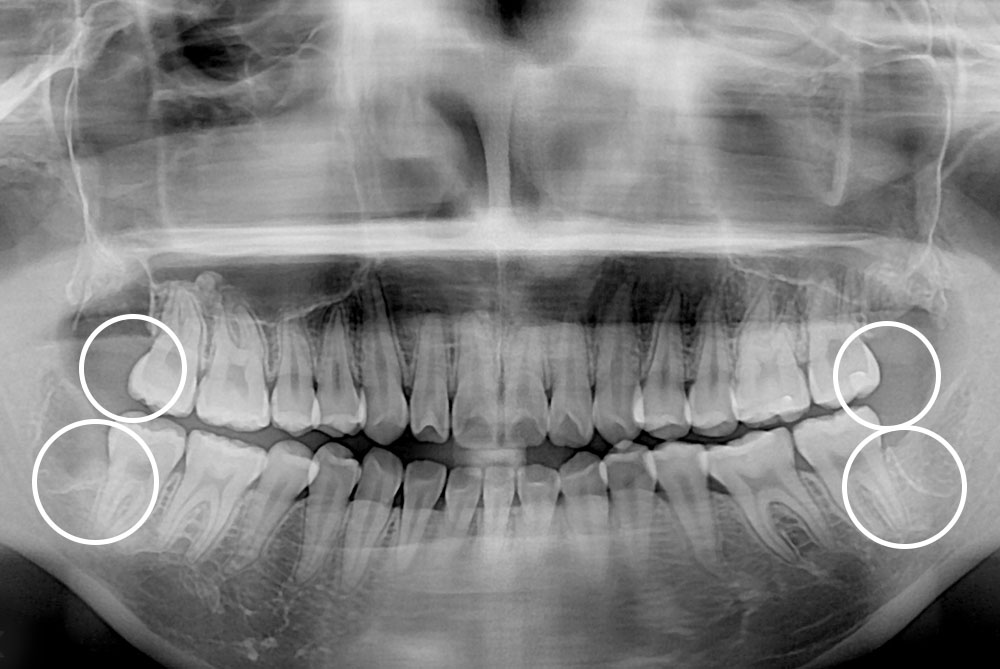

[사랑니] 매복 사랑니 발치

치료전 : 2019-02-25